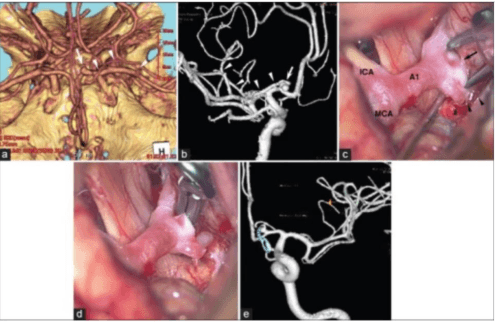

Abstract:Vision-language models have become increasingly powerful for tasks that require an understanding of both visual and linguistic elements, bridging the gap between these modalities. In the context of multimodal clinical AI, there is a growing need for models that possess domain-specific knowledge, as existing models often lack the expertise required for medical applications. In this paper, we take brain abnormalities as an example to demonstrate how to automatically collect medical image-text aligned data for pretraining from public resources such as PubMed. In particular, we present a pipeline that streamlines the pre-training process by initially collecting a large brain image-text dataset from case reports and published journals and subsequently constructing a high-performance vision-language model tailored to specific medical tasks. We also investigate the unique challenge of mapping subfigures to subcaptions in the medical domain. We evaluated the resulting model with quantitative and qualitative intrinsic evaluations. The resulting dataset and our code can be found here https://github.com/masoud-monajati/MedVL_pretraining_pipeline